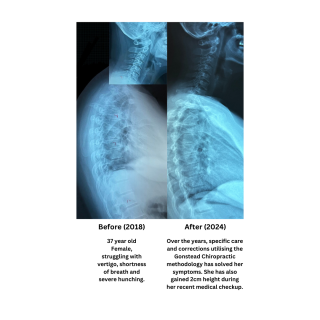

Reduced Hunching and Increment of 2cm Height